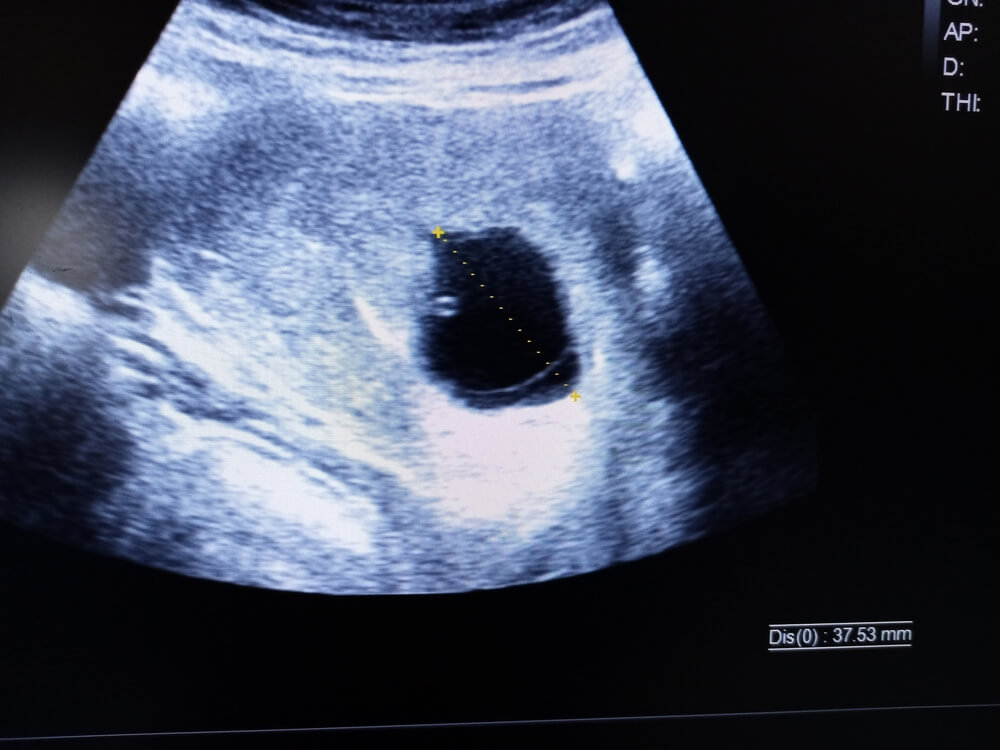

Ultrazvučni prikaz anembrionalne trudnoće na kojem se ne prikazuju ni plod ni žumanjčana vreća, nego samo prazna gestacijska vreća.

Ginekološkim pregledom će se ustanoviti prisutnost krvi u rodnici te eventualno nešto tvrđa maternica i stupanj otvorenosti vrata maternice. Ultrazvučnim pregledom će se prikazati unutar šupljine maternice prazna gestacijska vrećica, najčešće između 7. i 9. tjedna trudnoće.